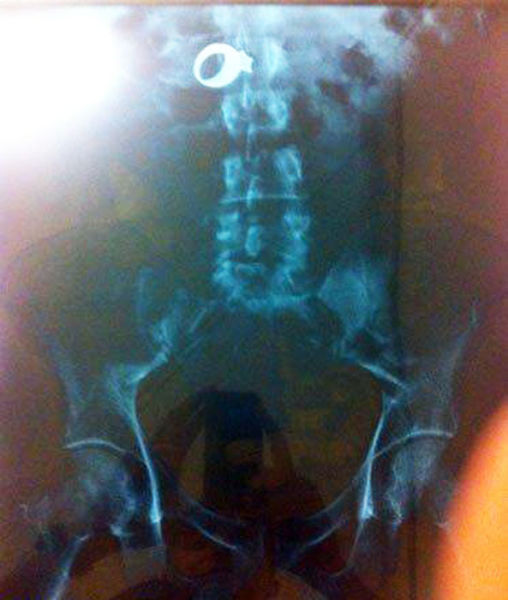

52-year-old Dutchwoman Margaret Daalman came to hospital complaining of stomach ache, and one glance at her X-ray shows why.Surgeons in Rotterdam in the Netherlands were astonished when X-rays showed 78 different items of cutlery in her stomach.